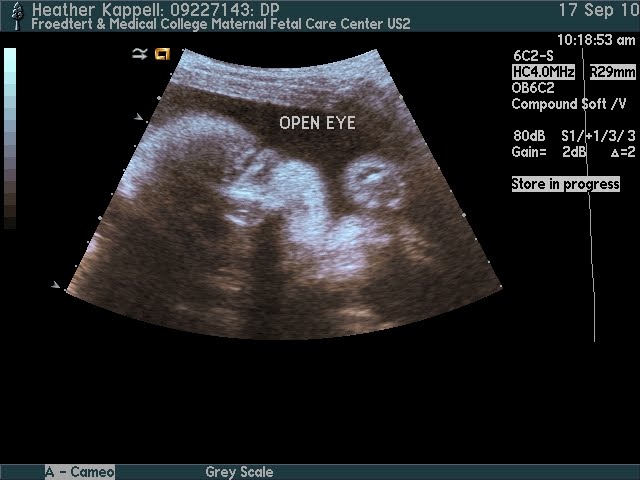

The last visit to the OB was on September 17 and this little guy is doing FANTASTIC! Below are some of his newest ultrasound pictures. On Friday, baby boy was measuring in at 3 lbs 7 oz! That is still a gain of one ounce a day since his last measurement 2 weeks prior. Still in the 69 percentile for his age (28w6d). The OB also stated that the next visit I "should" be able to have a date planned for induction! AHHH!! That means time is running out before this little one is due to arrive! The OB states that everything is perfect now. Because of living 2 hours away from the hospital where I will be delivering I had one of the nurses give me a tour of the labor & delivery area. I just wanted to see what kind of room I would be in. Nothing special but now I know what kind of accommodations we will have!